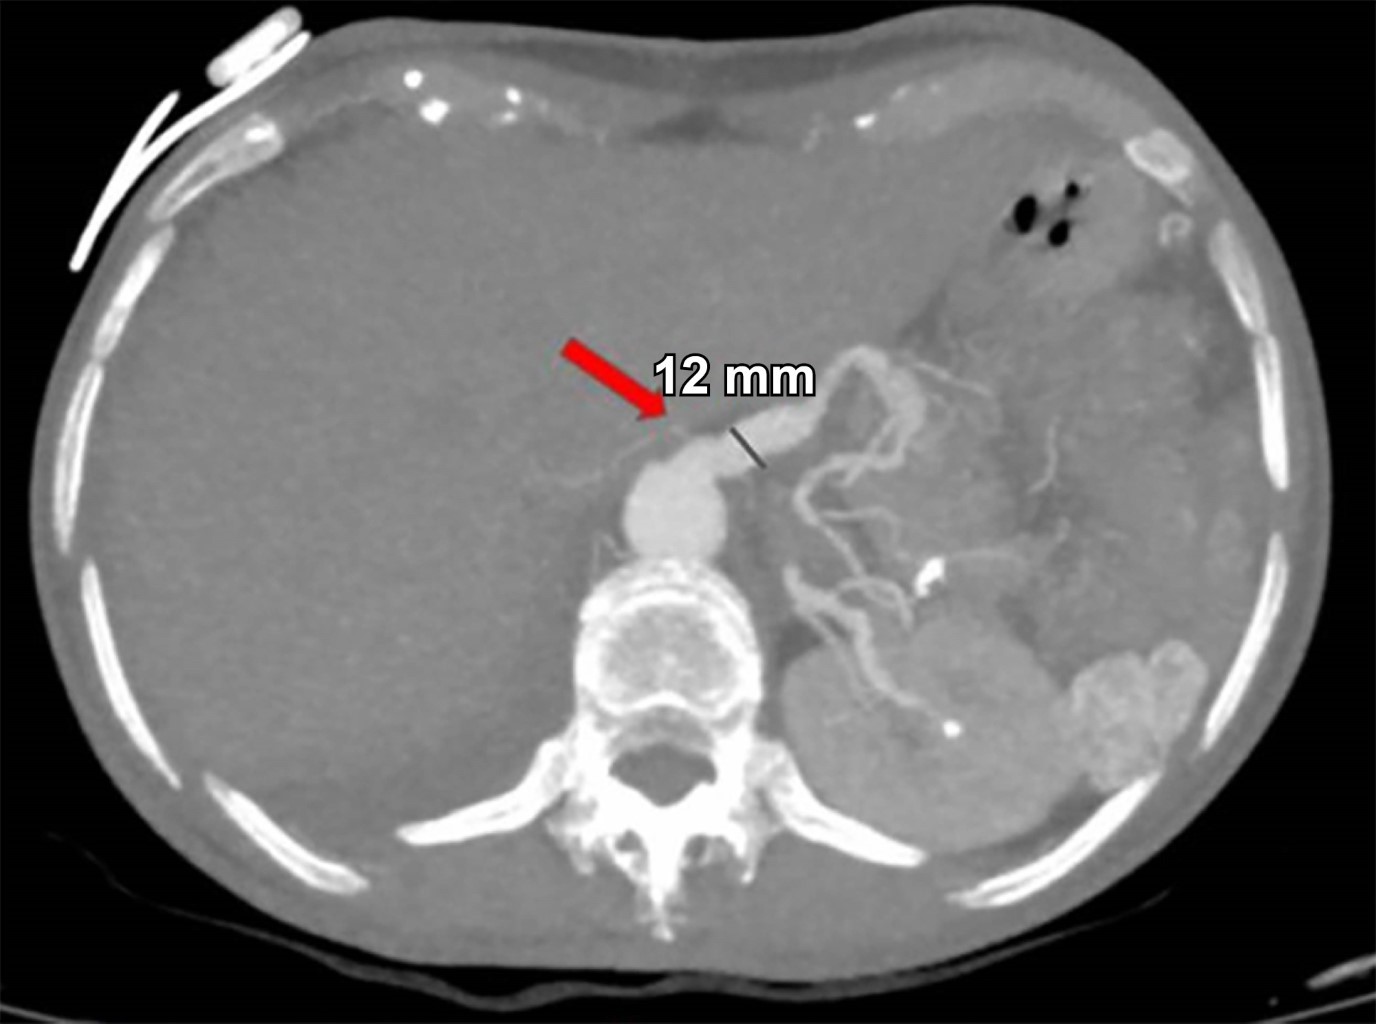

Mujer de 44 años quien 6 meses previos a su ingreso refiere disminución progresiva de la clase funcional debido a un soplo aórtico, por lo que se realizó cambio valvular con la necesidad de ser sometida a circulación extracorpórea y uso de vasopresores. Durante los primeros 10 días postquirúrgicos se diagnostica obstrucción intestinal, por lo que se realiza TC con hallazgo incidental de arteria esplénica (Figura 1) con dilatación aneurismática de hasta 12 mm, en un nuevo estudio de TC a las 24 horas (Figura 2) con ligero aumento del diámetro de aneurisma esplénico hasta 15 mm, pasadas 96 horas solicita nueva TC (Figura 3) y se evidencia mejor definición de la dilatación aneurismática de la arteria esplénica con diámetro actual de 15 mm (previamente de 12 mm). Con los hallazgos tomográficos previamente descritos, se pudo observar la evolución del proceso de dilatación aneurismática con ruptura contenida por el parénquima pancreático, la paciente cursó con un cuadro de obstrucción intestinal con desimpactación endoscópica y dolor abdominal, por lo que seguramente se enmascaró el cuadro clínico.

En nuestro caso, la ruptura de la arteria esplénica en la cual la hemorragia es contenida por el parénquima pancreático logrando sellar el defecto sin presentar pancreatitis y sólo dejando atrás una hipodensidad en el parénquima pancreático subyacente, es extremadamente rara.

Figura 3